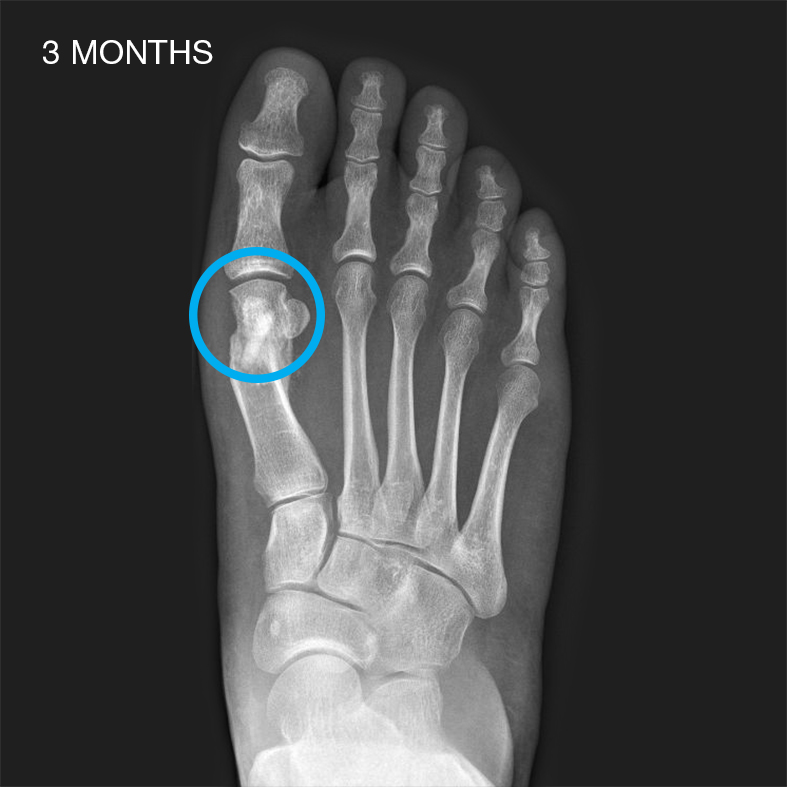

Case reports with Shark Screw®

Shark Screw® shows its full potential when it comes to non-union cases. The creeping substitution can significantly boost bone healing – just trust biology.

Shark Screw® can be used in the space of Foot & Ankle (e.g. bunionectomy, MTP1 fusion, Hammertoe correction, IP-Fusion, TN-Fusion, Lapidus Arthrodesis, Lisfranc Joint Fusions, Jones Fx, Weil Osteotomies, DIP Fusions, Non-Unions, Medial Malleolus Osteotomies, Calcaneus Osteotomies, Subtalar Fusions etc.). Shark Screw® can be also utilized in various indications in Hand & Wrist surgery (e.g. DIP and PIP Fusions, MCP1 Arthrodesis, Scaphoid Fx and Non-Unions, Metacarpal Fusions, Four Corner Fusions, Distal Radius Fx etc.)